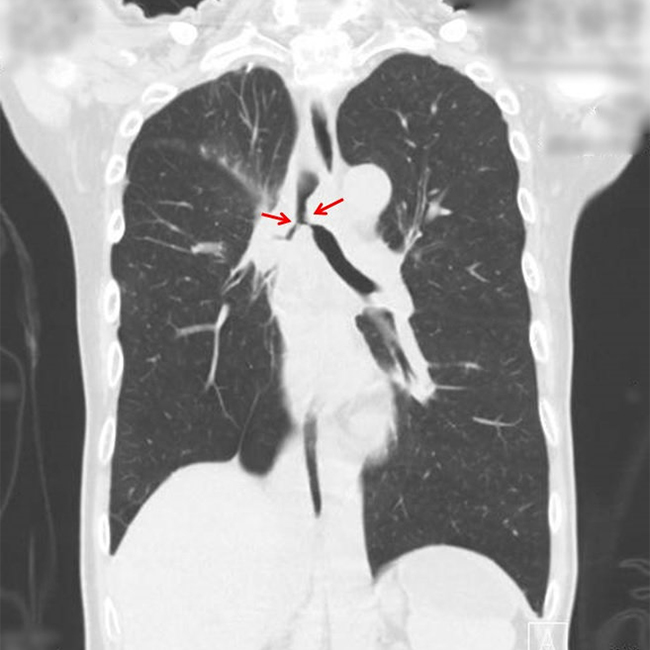

がんや結核後遺症などが原因で気管支内腔が狭くなり呼吸が苦しくなった場合にステント留置術が行われることがあります。メスを用いることなく呼吸困難を解消することが目的です。軟性または硬性の気管支鏡を用いて気道内にステントを挿入し狭くなった気管・気管支を拡張します。レーザー治療や風船による拡張術が併用されることもあります。通常の麻酔や気道確保が困難な場合は、麻酔科医・臨床工学士・呼吸器内科医など多くのスタッフと協力して一時的な体外式膜型人工肺(ECMO・エクモ)も併用して安全確実に手術を行います。